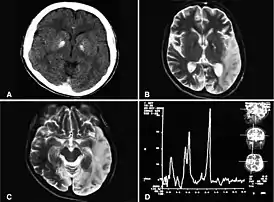

![]() Двусторонняя кальцификация базальных ганглев, легкая атрофия мозжечка, ишемические изменения, повышение лактата. Abu-Amero et al., 2009[1] | |